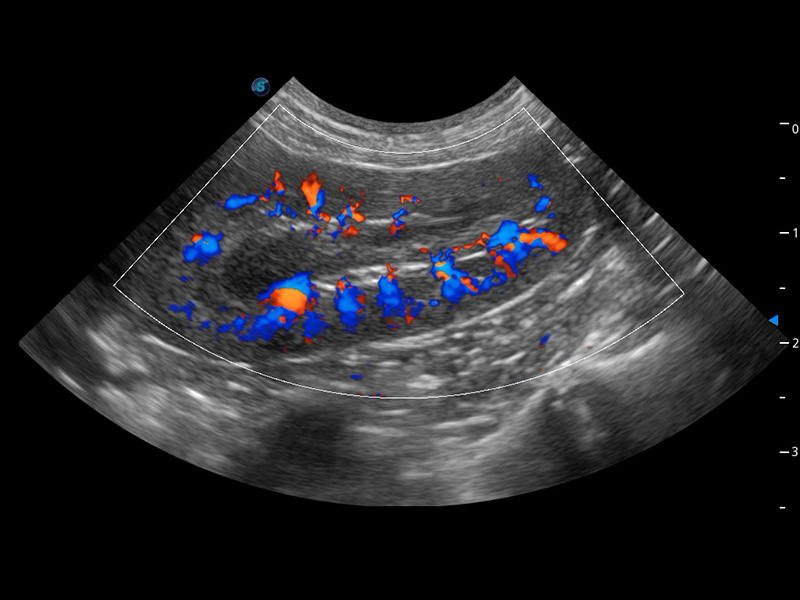

ProPet 60 作為一款高端臺(tái)式動(dòng)物超聲設(shè)備,為動(dòng)物醫(yī)生的日常診斷提供了一系列貼合動(dòng)物臨床需求、解決臨床實(shí)際問題的高級(jí)成像功能。憑借全系列高清探頭,滿足醫(yī)生對(duì)腹部、心臟、生殖、淺表、肌骨等成像的所有需求,切實(shí)幫助您提升檢查效率,提高診斷信心。